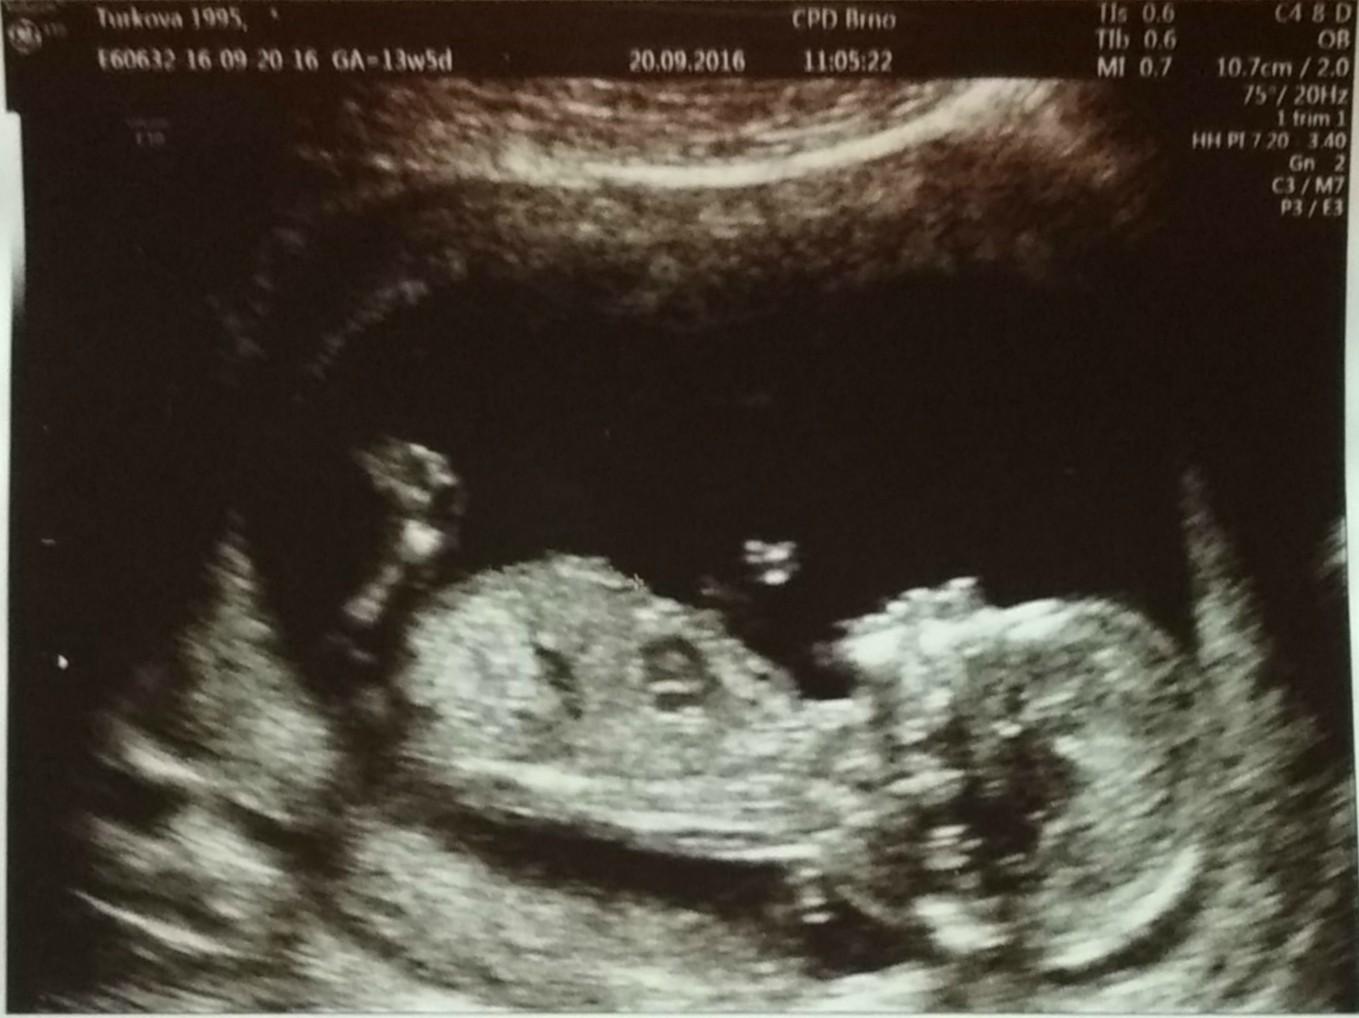

první screening...nejkrásnější pocit, když jsem ho viděla jak se tam mrská jako rybička :) pan doktor nám řekl že je to chlapeček, ani nemusel, ta jeho výbavička byla nepřehlédnutelná :D